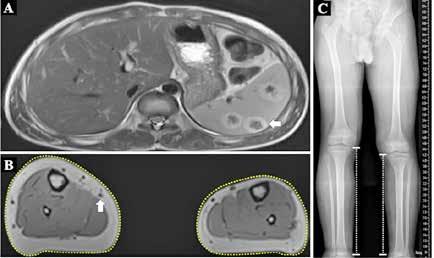

Todas las malformaciones capilares eran congénitas y el paciente refería que habían crecido de manera proporcional al resto del cuerpo, aunque el tamaño de las extremidades había aumentado paulatinamente en los últimos años. El niño no refería dolor ni presentaba déficit neurológico, cognitivo, motor o sensitivo alguno. Sin embargo, la dismetría y el sobrecrecimiento de miembros inferiores limitaba ligeramente la deambulación y el calzado. Se realizó una resonancia magnética toracoabdominal y de extremidades que informó múltiples dilataciones venosas en tronco y miembros inferiores con imágenes ocupacionales en bazo, compatibles con hemangiomas, y la telemetría de extremidades inferiores confirmó una diferencia de longitud de 3,5 cm (Figura 3). No se identificaron malformaciones venosas, linfáticas ni combinadas. Se extirpó el dedo supernumerario identificando una hipertrofia tisular y mediante tecnología de secuenciación masiva (NGS) se estudió el ADN de sangre periférica (A), de tejido afecto sin cultivar (B) y de fibroblastos de tejido afecto cultivados (C). En un 33% de las secuencias de la muestra B y en un 47% de las secuencias de la muestra C se detectó la presencia de la variante c.353G>A p.(Gly118Asp) localizada en el exón 3 del gen PIK3CA (NM_006218.3). En sangre periférica no se identificó dicha mutación. Esta variante fue comprobada mediante amplificación por PCR y secuenciación bidireccional del exón 3 y sus regiones intrónicas adyacentes.

Dado el resultado del estudio molecular, el paciente fue diagnosticado de malformación capilar difusa dentro del espectro de sobrecrecimiento relacionado con PIK3CA (en inglés, PROS). Para completar el diagnóstico diferencial con algunos síndromes dentro del PROS que asocian alteraciones encefálicas, se realizó una resonancia craneal que descartó anomalías a este nivel. Actualmente el sobrecrecimiento se encuentra estable, el paciente está en seguimiento multidisciplinar y a la espera de epifisiodesis por la dismetría de miembros inferiores, tras lo cual se valorará la terapia biológica con inhibidores de la vía de señalización PI3K/AKT/m-TOR, ya que ante un eventual empeoramiento de las dilataciones venosas o la hipertrofia, el enfermo se beneficiaría de la inmunoterapia dirigida y/o adyuvancia quirúrgica.

Figura 3.

A: Resonancia magnética abdominal con lesiones esplénicas hipercaptantes sugestivas de hemangiomas (flecha). B: Resonancia de extremidades inferiores con aumento del volumen de partes blandas y óseas en ambas piernas, especialmente al lado derecho (líneas de puntos) y dilataciones venosas en piernas (flecha). C: Telemetría que confirma dismetría de miembros inferiores (3,5cm).